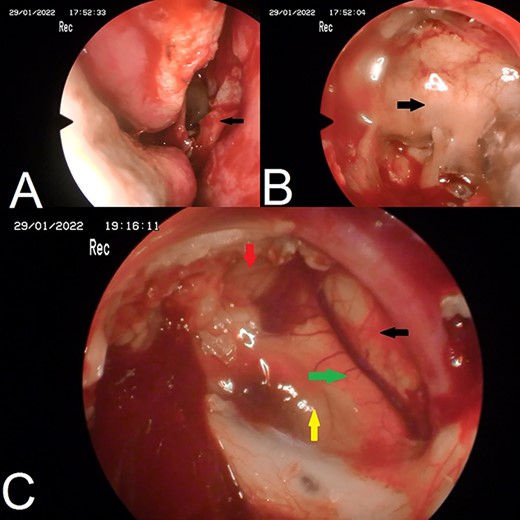

A 22-year-old caucasian male was admitted to neurosurgery department with a history of chronic headache and 8-month history of bilateral visual acuity deterioration. Ophthalmologic evaluation revealed light perception on the right side and hand motion on the left side. Fundus examination showed bilateral temporal optic nerve pallor. Eye movement was normal. The patient had no focal neurological deficits. Laboratory tests were unremarkable. Magnetic resonance imaging (MRI) revealed a sellar and suprasellar well-defined cystic lesion with irregular margins, measures about 2.6 × 3.3 × 4 cm. The mass was hypointense in T1-weighted images (T1WI) and hyperintense in T2-weighted images (T2WI) with restriction in diffusion-weighted images (DWI). The mass was compressing the optic chiasm and surrounding the right optic nerve and pituitary stalk (Fig. 1). The patient underwent an endoscopic surgery and transnasal trans-sphenoidal approach was used to resect the cyst. A drilling of the sphenoid sinus septations was done. Using the Kerrison, the superior half of the posterior bony wall of the sphenoid sinus was removed to reach the sellar and suprasellar region. The dura was incised widely. We observed a sac within the sella compressing the pituitary gland. The sac was extended to the suprasellar region compressing the optic chiasm and reached to the floor of the frontal lobe anteriorly. The sac was opened and completely evacuated of cheesy materials. After evacuation of the cyst, we detached the epidermoid capsule from the pituitary gland and displaced the sac upward into the suprasellar region. A smooth dissection was applied to detach the capsule of epidermoid from the optic chiasm down to the posterior frontal lobe. We used a bipolar diathermy to coagulate small bleeding vessels. A 30° endoscope was used to confirm a complete resection of the sac (Fig. 2). An underlay graft from fascia lata of musculus quadriceps femoris was used to cover the defect of skull base and reinforced with fat tissue, nasoseptal flap and thrombin-soaked collagen sponges. Pathology revealed sheets of keratin indicating an EC (Fig. 3). Two days after surgery, the patient experienced sudden onset of high-grade fever and neck stiffness. The CSF opening pressure was normal and cultures for bacteria, mycobacteria and fungi were negative. The cell count and glucose and protein levels were normal. Based on the CSF findings, a diagnosis of aseptic meningitis was established. Conservative management was applied and the meningitis was resolved. Seven days after surgery, the patient showed partial recovery in visual acuity of the left eye with no improvement on the right side. On 6-month follow-up, the patient remained stable and no complication was developed. Brain MRI demonstrated no evidence of residual or recurrent lesion.

Endoscopic images. (A) nasoseptal flap; (B) posterior bony wall of sphenoid sinus; (C) complete resection of epidermoid cyst, green arrow: optic chiasm, yellow arrow: pituitary gland, red arrow: internal carotid artery, black arrow: anterior brain.